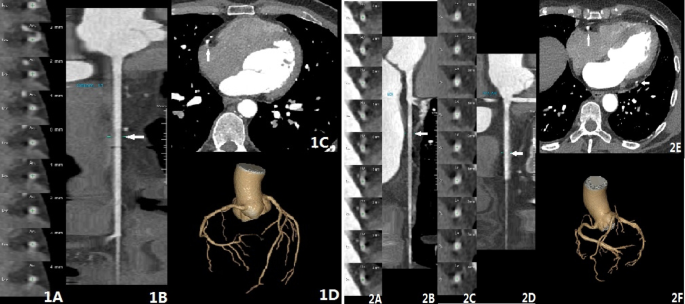

As shown in Fig. 2, subjective scoring results demonstrated typical images with scores ranging from 2 to 5 points (Figs. 2 A–2D). The morning group exhibited a significantly higher excellent image quality rate of 87.9% compared to 74.1% in the afternoon group (Z = -4.453, P < 0.001). Table 3 presents the excellent image quality rates for both groups across different heart rate intervals. For instance, at HR ≤ 60 bpm, the morning group had an excellent rate of 98.4% (124/126) versus 95.7% (90/94) in the afternoon group. In the 60 < HR ≤ 65 bpm interval, the morning group maintained an excellent rate of 97.5% (77/79), while the afternoon group decreased to 83.4% (57/66). The difference in excellent rates significantly increased when HR > 75 bpm. The Wilcoxon Signed-Rank Test revealed statistically significant differences between the morning and afternoon groups across various HR ranges before and after medication.

CCTA examination showed different types of artefacts and scoring results. Patient 1 (1 A, 1B, 1 C, 1D) – 1 A shows the axial image at the position marked by the arrow in 1B (RCA curved CPR reconstruction). 1 C is the CCTA axial image, where the contour of the RCA segment is unclear, with a comet-tail blur at the arrow position. 1D (VR image) shows the overall continuity of the CCTA with no layering or motion artefacts, indicating that only the RCA segment exhibits artefacts, with a score of 4. Patient 2 (2 A, 2B, 2 C, 2D, 2E, 2 F) – 2 A and 2 C correspond to 2B (RCA curved CPR reconstruction) and 2D (LCX curved CPR reconstruction) at the marked positions in the axial images. 2E is the CCTA axial image, where the contours of both the RCA and LCX vessels are unclear, with comet-tail blur present. 2 F (VR image) demonstrates the overall continuity of the CCTA with no layering or motion artefacts, indicating artefacts in both the RCA and LCX segments, resulting in a score of 3.